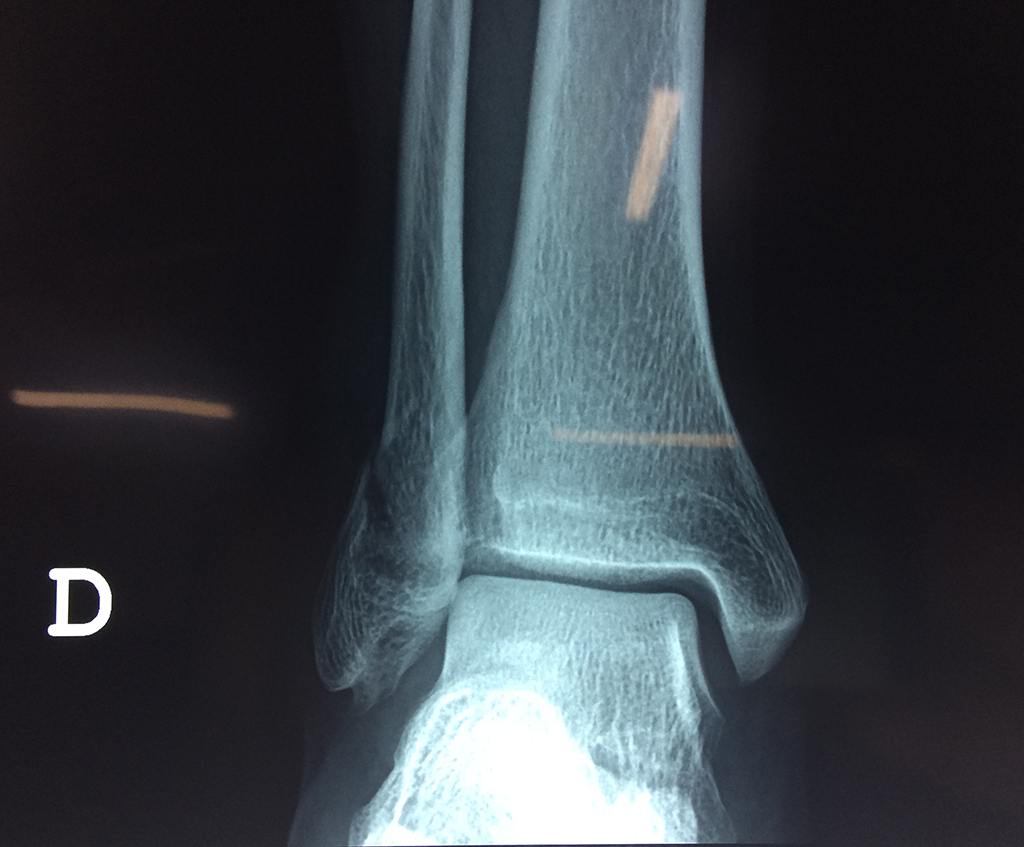

Una fractura de tobillo es la rotura de uno o más de los huesos del tobillo. Estas fracturas pueden ser:

Algunas fracturas de tobillo pueden requerir cirugía si:

• Los extremos de los huesos están desalineados entre sí (desplazados).

• La fractura se extiende hasta la articulación del tobillo (fractura intra-articular).

Cuando se necesita cirugía, es probable que esta implique el uso de clavijas de metal, tornillos o placas para sostener los huesos en su lugar mientras la fractura se consolida. Los elementos de soporte pueden ser temporales o permanentes.